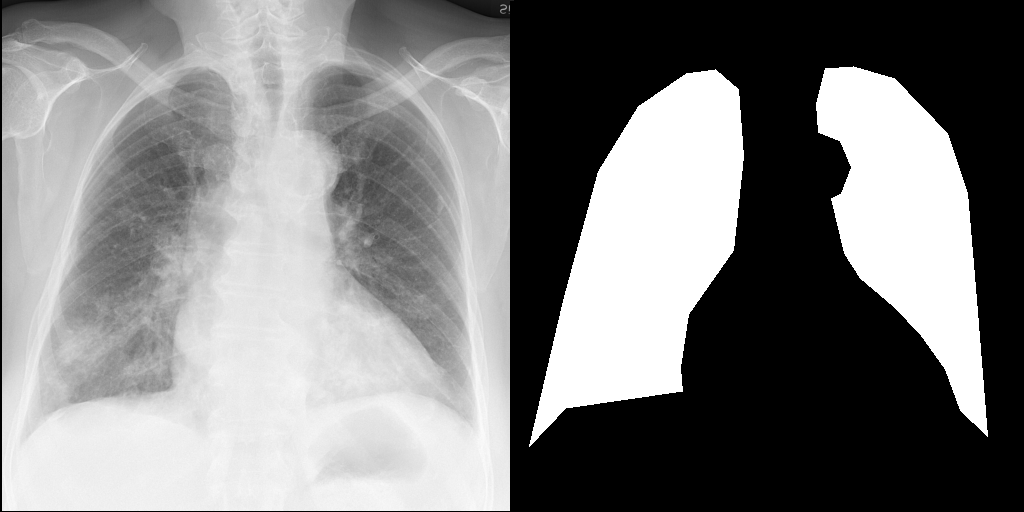

Let's load an example image of a patient with influenza.

import requests

from PIL import Image, ImageDraw

from torchvision import transforms

def download_sample_image() -> Image.Image:

"""Download chest X-ray with CC license."""

base_url = "https://upload.wikimedia.org/wikipedia/commons"

image_url = f"{base_url}/2/20/Chest_X-ray_in_influenza_and_Haemophilus_influenzae.jpg"

headers = {"User-Agent": "RadEdit"}

response = requests.get(image_url, headers=headers, stream=True)

return Image.open(response.raw)

image = download_sample_image()

input_image = transforms.Compose([transforms.Resize(512), transforms.CenterCrop(512)])(image)

right_lung_coords = [(19, 445), (53, 299), (88, 170), (128, 105), (176, 72), (205, 68), (228, 88), (233, 155), (223, 249), (178, 313), (170, 366), (172, 390), (55, 407)]

left_lung_coords = [(477, 435), (466, 298), (457, 192), (437, 132), (384, 77), (343, 65), (315, 67), (306, 102), (308, 131), (330, 140), (341, 166), (331, 192), (321, 197), (334, 252), (350, 277), (383, 305), (410, 333), (435, 368), (450, 409)]

# Create a blank image with the same size as the original image

lung_mask = Image.new("L", (512, 512), 0)

# Draw the filled shape using the coordinates

draw = ImageDraw.Draw(lung_mask)

draw.polygon(right_lung_coords, fill=255)

draw.polygon(left_lung_coords, fill=255)

For this example, we will remove the visual appearance of influence from the lungs, while preventing changes from happening to the rest of the image. To do this, we create a mask of the lung regions and use this as the edit_mask which defines the region we wish the editing prompt to be applied to. Since we want the rest of the image to remain unchanged, we use the inverse as the keep_mask which defines the region where edits are discouraged from taking place.

from PIL import ImageOps

edit_mask = lung_mask

keep_mask = ImageOps.invert(lung_mask)